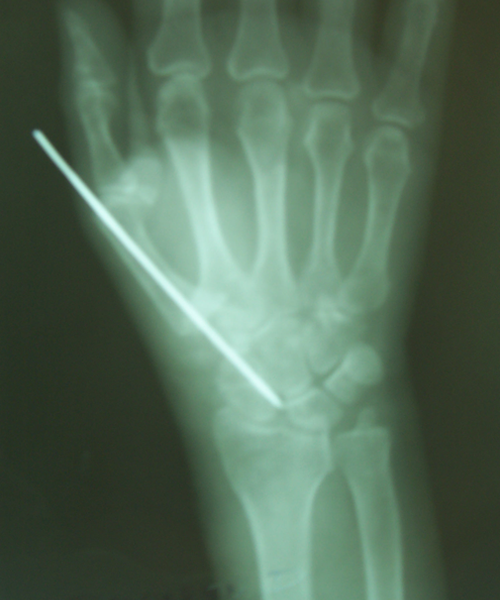

Case:5 RollTendon Arthroplasty

Arthroscopy Surgeon in Ahmedabad|Limb Reconstruction Doctor

Pre-Op

Arthroscopy Surgeon in Ahmedabad|Spine Treatment In Jaipur

Post-Op